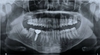

La radiographie panoramique

C'est le cliché de routine qui permet d'appréhender l'ensemble de la dentition et des structures sous-jacentes.

Il est réalisé en début de traitement pour poser le diagnostic et en cours de traitement pour contrôler le bon déroulement de celui-ci.

Nous sommes équipés pour réaliser ce cliché sur place dans notre cabinet.